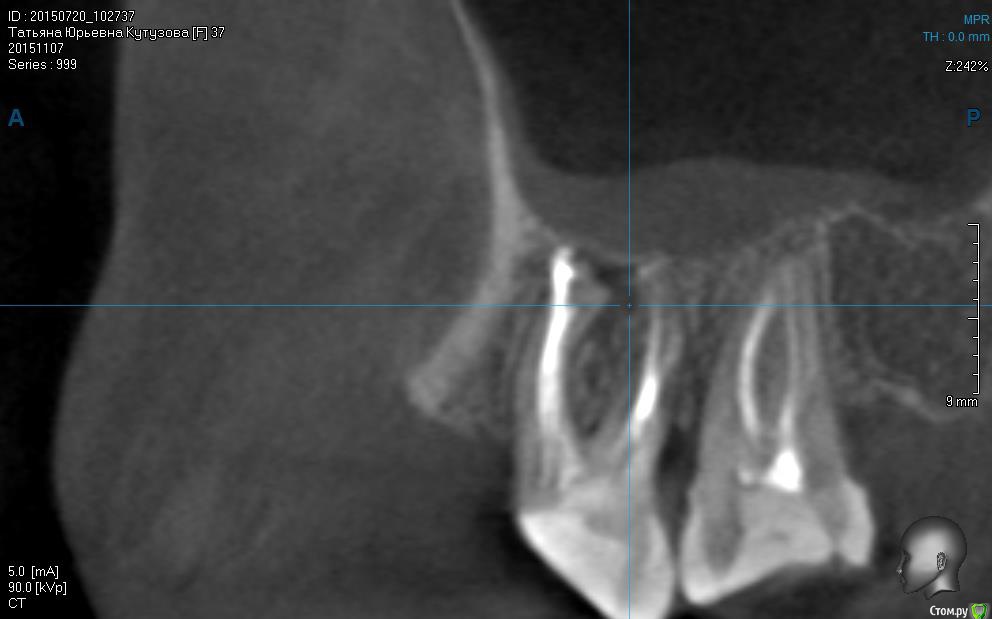

татьяна tat Опубликовано 16 декабря, 2015 Автор Поделиться Опубликовано 16 декабря, 2015 первый снимок после лечения,второй до! может кто нибудь сказать что то по этому поводу? Ссылка на комментарий

DmitrySH Опубликовано 16 декабря, 2015 Поделиться Опубликовано 16 декабря, 2015 Попытка лечения не принесла результата. Удалять. Ссылка на комментарий

татьяна tat Опубликовано 16 декабря, 2015 Автор Поделиться Опубликовано 16 декабря, 2015 Попытка лечения не принесла результата. Удалять.уважаемый доктор!!!!!!! скажите,умоляю....почему удалять? что с ним? боли у меня из-за него все таки?? Ссылка на комментарий

DmitrySH Опубликовано 16 декабря, 2015 Поделиться Опубликовано 16 декабря, 2015 Нет, я не могу знать откуда боли, от 6 зуба или нет .Но на данном зубе была и есть есть гранулема, зуб попытались вылечить, не вышло. Пытаться еще раз провести лечение - нет смысла. Ссылка на комментарий

татьяна tat Опубликовано 16 декабря, 2015 Автор Поделиться Опубликовано 16 декабря, 2015 Нет, я не могу знать откуда боли, от 6 зуба или нет .Но на данном зубе была и есть есть гранулема, зуб попытались вылечить, не вышло. Пытаться еще раз провести лечение - нет смысла.скажите пожалуйста....а мне кажется..или есть перфорация? Ссылка на комментарий

DmitrySH Опубликовано 16 декабря, 2015 Поделиться Опубликовано 16 декабря, 2015 Возможно, но вопрос в другом, канал не удалось полностью обработать. Ссылка на комментарий

Shaid Опубликовано 25 декабря, 2015 Поделиться Опубликовано 25 декабря, 2015 Постойте! Два последних снимка, что Вы скинули - с одинаковой датой. Контрольный снимок делается минимум через 6 месяцев, чтобы увидеть хоть какие-то положительные или отрицательные изменения. Ссылка на комментарий

татьяна tat Опубликовано 25 декабря, 2015 Автор Поделиться Опубликовано 25 декабря, 2015 (изменено) Постойте! Два последних снимка, что Вы скинули - с одинаковой датой. Контрольный снимок делается минимум через 6 месяцев, чтобы увидеть хоть какие-то положительные или отрицательные изменения.как это с одной??? вы что??? кт до перелечивания был сделан в июле....а после перелечивания в ноябрее....и как мне теперь постоять....если зуб мне удалили........ и чего было ждать,если DmitrySHсказал,что канал не удалось перелечить....и хирург на консультации сказал,что зуб на удаление...... Изменено 25 декабря, 2015 пользователем татьяна tat Ссылка на комментарий